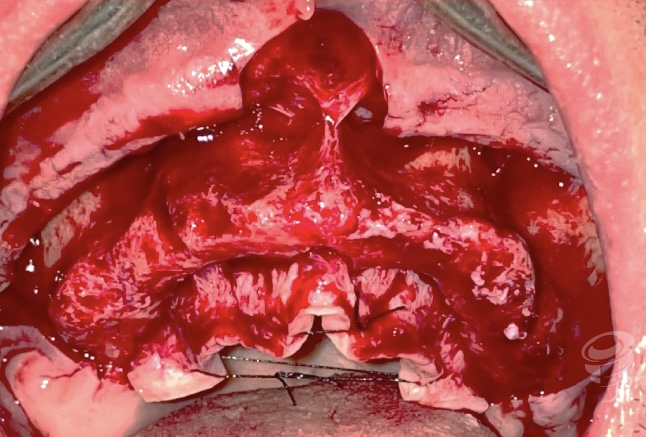

Imagen 16 – Imagen Intraoperatoria

Imagen 17 – Post-Edentación Completa

Imagen 18 – Cresta ósea Post-Edentación

Protocolo en pacientes periodontales severos: Edentación + Implantes cigomáticos y convencionales inmediatos + Carga inmediata (CBCT y aspecto intraoperatorio de la cresta maxilar). (Imagen 14-25)

Hoy en día este protocolo nos permite abordar casos con enfermedad periodontal severa en pacientes con poco volumen óseo en sectores posteriores, que no quieren estar sin dientes, con protocolos de implantes inmediatos a extracción y carga inmediata con excelentes resultados a largo plazo. (Imagen 14-25)